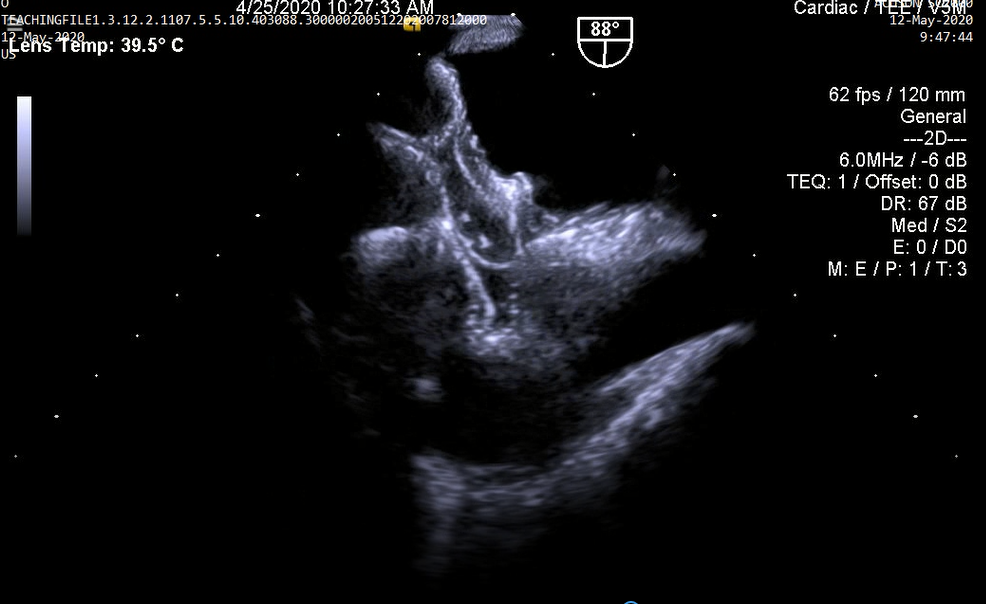

1.Huyết khối gây kẹt van hai lá cơ học: